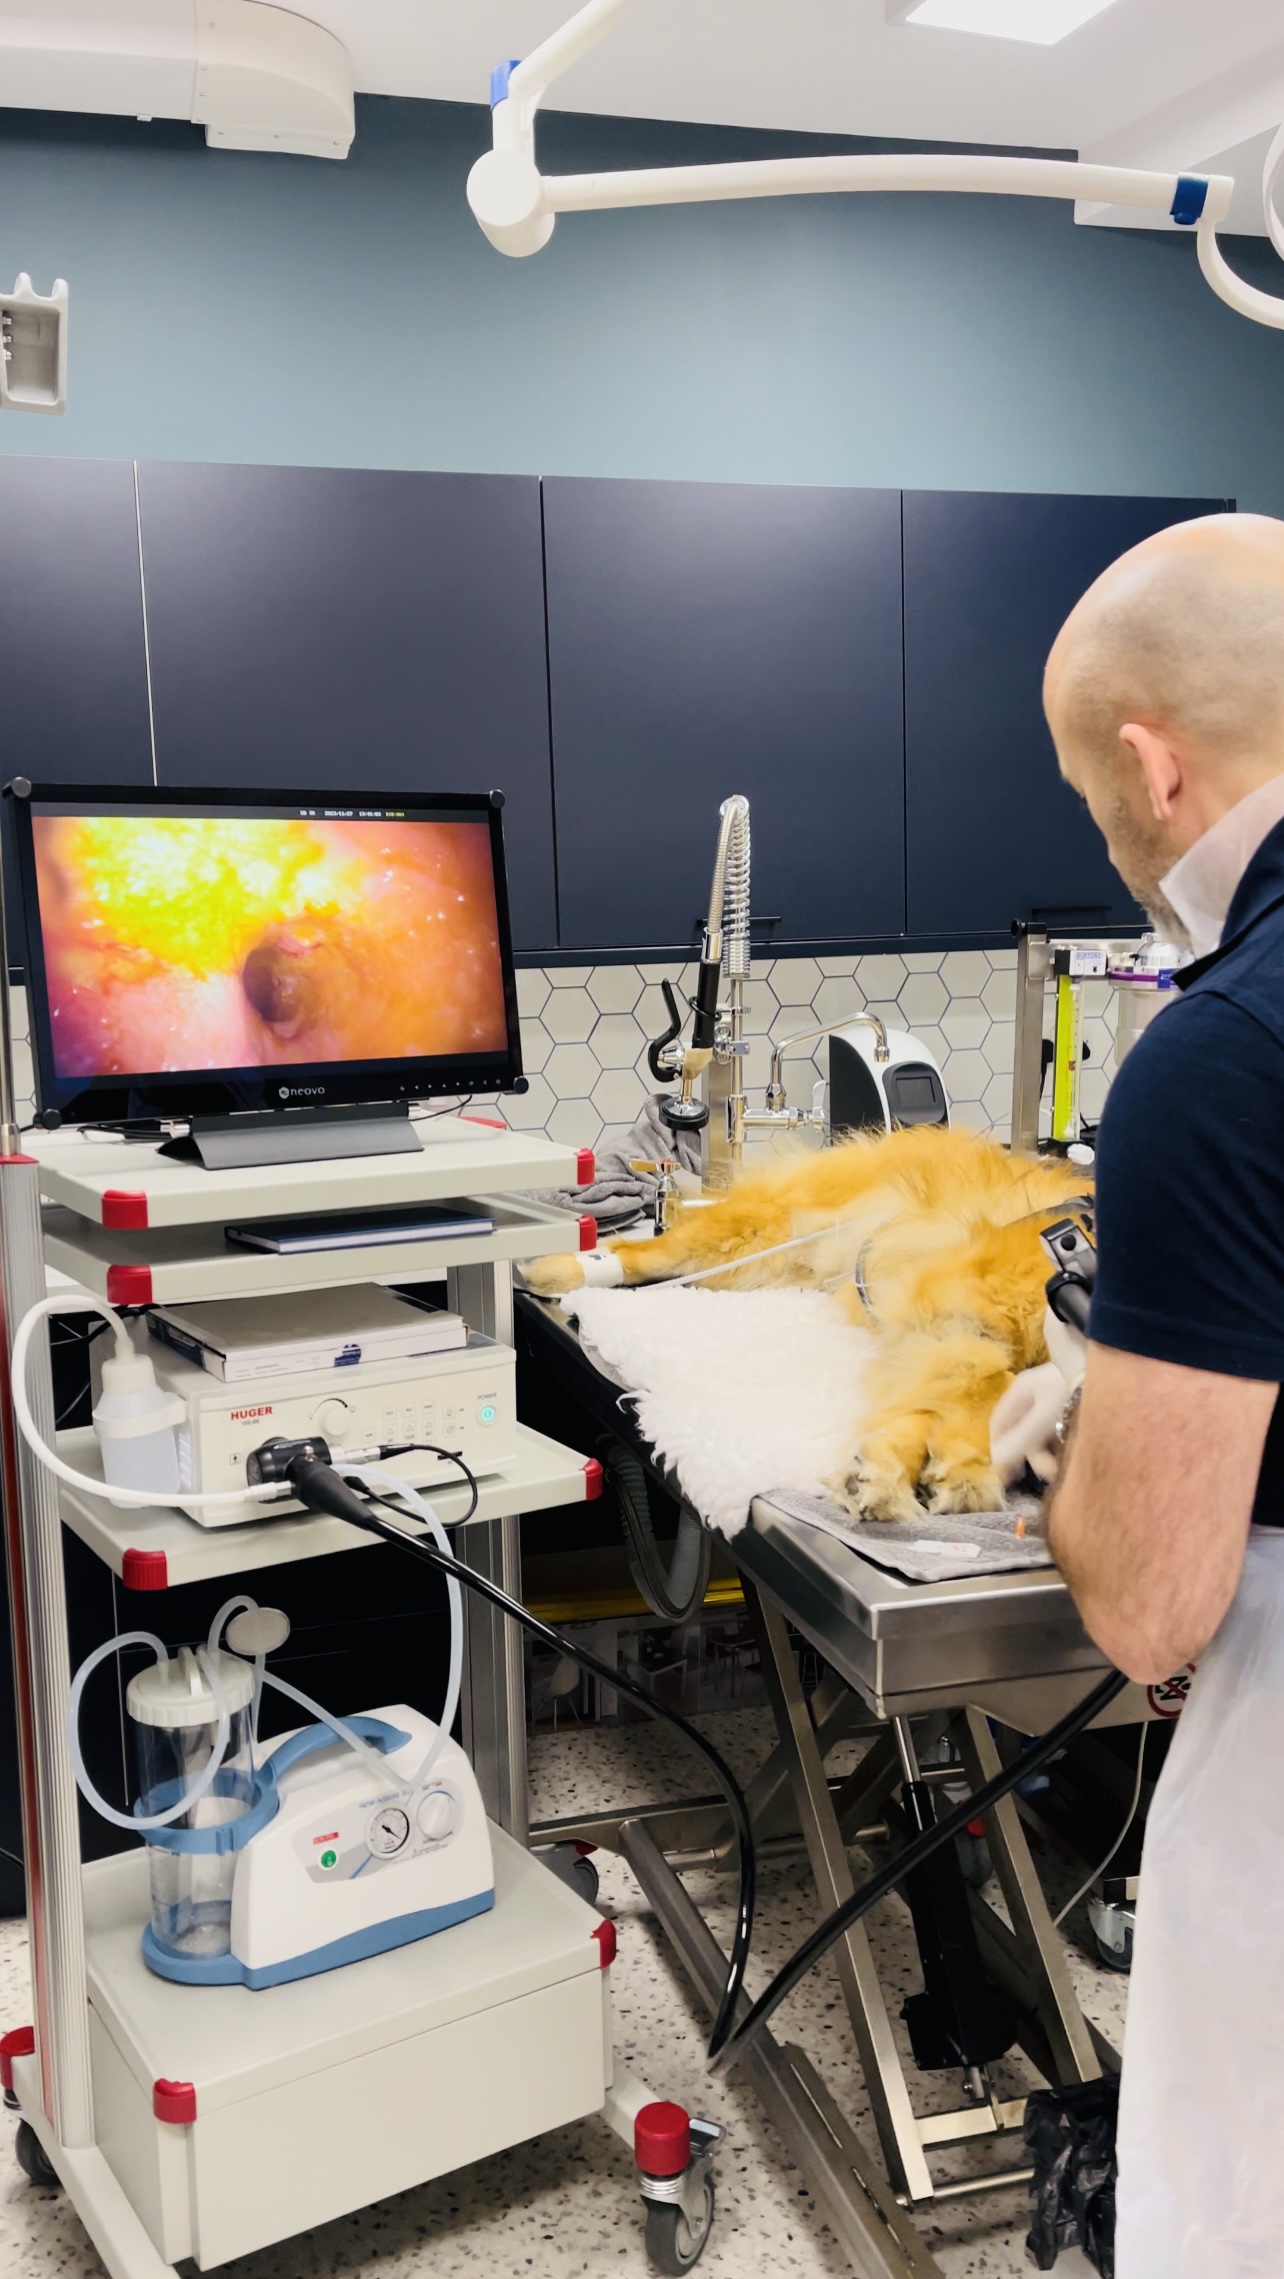

Acute and chronic, vomiting and diarrhoea are very common presentations for dogs and cats in a small animal vet practice. There can be numerous causes including infections and parasites, particularly in younger pets, through to food allergy and inflammatory bowel disease (IBD) in others. Sudden onset illness is much easier to appreciate, with chronic disease the symptoms can be much more insidious. Poor body condition, intermittent vomiting and eating grass or a soft stool can be more subtle signs. Approximately, 80% of “fussy” dogs also have disease in their digestive tract. Cats that vomit every 2-4 weeks also nearly always have gut disease. In many patients, the problem goes unnoticed and untreated for years until the condition escalates or potentially changes to cancer. At Whisker & Woof, we actively screen for these problems in our annual check-ups so that we can help your pet at an early stage. Our Head Vet has a personal interest in gastroenterology and we have the endoscopy equipment on site to make a diagnosis and get your pet back on track and living life to the full.

Endoscopy

At Whisker & Woof, we have invested in rigid and flexible endoscopes that enable us to examine noses and bladders, through to the lungs and the digestive tract in both dogs and cats. We also have the training and experience to operate these sophisticated diagnostic tools, and use them purposefully to take samples and get to a diagnosis.